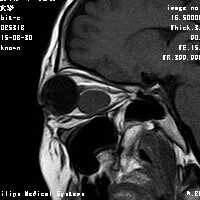

女,54岁,头痛头晕月余,无眼部症状及视力异常。 影像表现:右侧眼球后方占位病变,考虑海绵状血管瘤可能性大,鉴别:视神经鞘瘤、脑膜瘤及炎性假瘤。 病例点评:眼眶内血管瘤是较常见的良性肿瘤,其中以海绵状血管瘤最常见。可发生于任何年龄,主要表现为眼球突出及偏位,在低头或哭泣时可有突眼加重。可经眶缘触及具有压缩性的肿块。视力损害多较缓慢。肿块大多位于肌锥内,其次为肌锥外,平扫呈边界清楚的圆形、卵圆形或分叶状肿块,增强扫描呈缓慢进行性显著强化为其特征性表现。